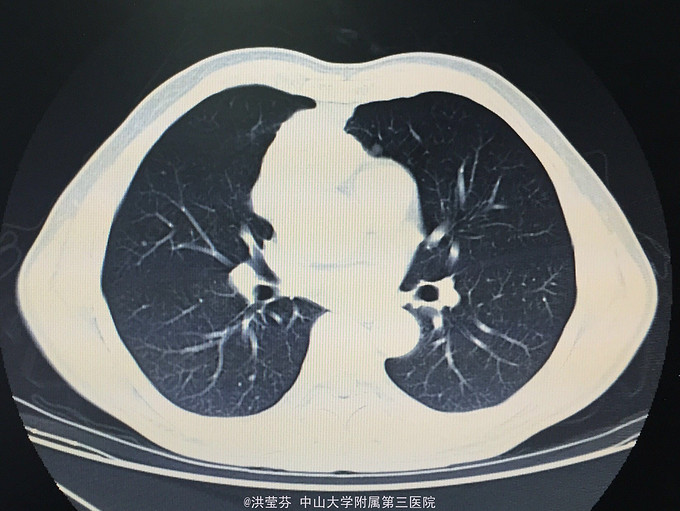

查体:KPS 60分,BSA 1.83m2,T 38.5℃,全身浅表淋巴结未触及明显肿大,胸壁可见浅表静脉曲张,呼吸急促,左下肺、右中下肺呼吸音明显减弱,其余肺野呼吸音促,可闻及少许实性啰音,心率110bpm,律齐,腹软,全腹无压痛、反跳痛,未扪及明显包块,肝脾肋下未触及,移动性浊音(——),肠鸣音正常,4次/分,双下肢无凹陷性水肿。 辅助检查:血常规无特殊,生化转氨酶稍升高,低钠低氯,CRP 227.9mg/L,凝血四项:Fib 8.14g/L。复查胸部CT提示:1.胸腺癌并纵膈淋巴结及双肺多发转移瘤,右心房、上腔静脉受侵并癌栓形成,病变较前进展。2.双肺炎症,以右肺为著。3.双侧胸腔及心包积液。上腹部CT提示:1.下腔静脉早显并肝表面多发侧支形成,考虑右心流出道阻塞所致;腹壁静脉曲张。头颅MR提示右侧颞叶强化灶,结合病史,考虑转移瘤,伴瘤灶少量出血可能,瘤周脑水肿。